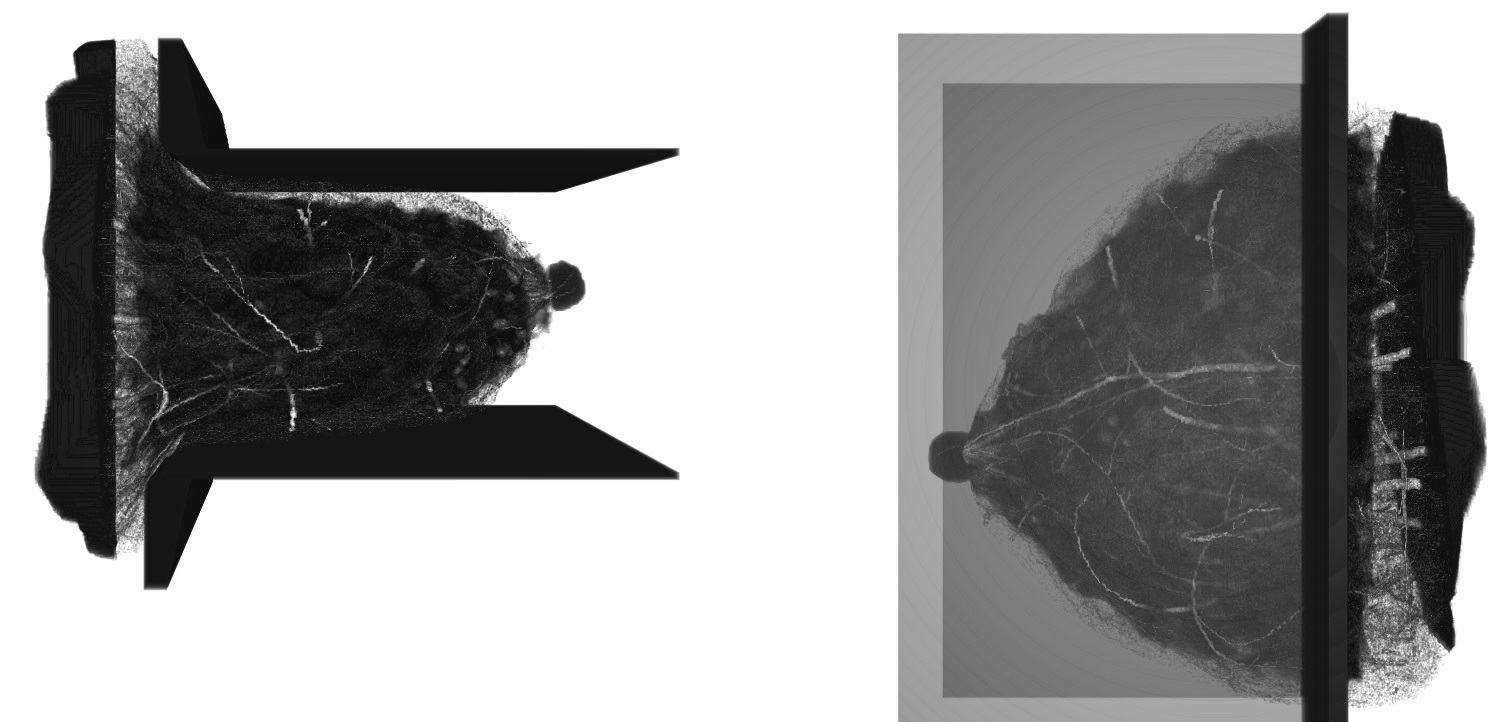

../_images/Breast_phantom.jpg

Example of voxelized breast phantom generated by VICTRE.